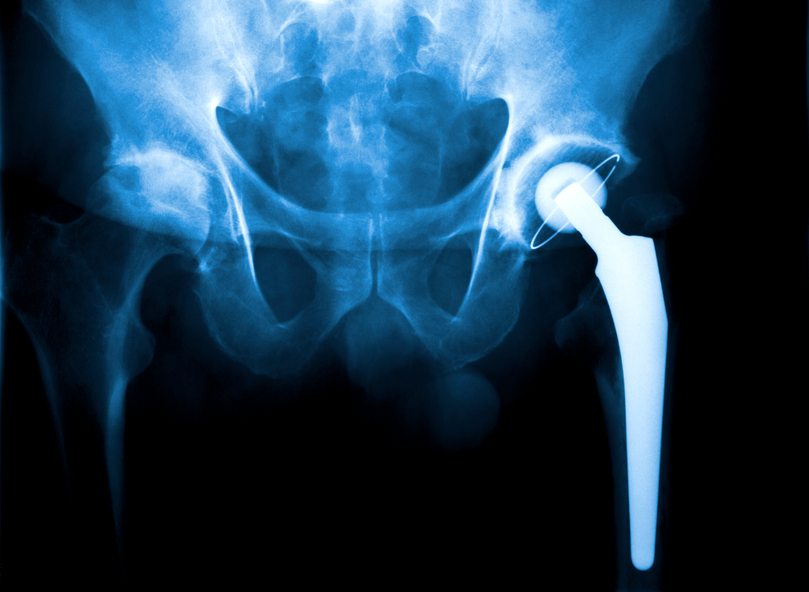

The Total hip replacement (or hip arthroplasty) technique has become widespread in recent years, in response to the need for improving hip joints that have been damaged by injury or arthritis. This is a surgical procedure where the diseased or damaged cartilage and bone of the hip joint is surgically replaced with artificial materials. The normal hip joint is a ball and socket joint. The socket is a “cup-shaped” component of the pelvis called the acetabulum. The ball is the head of the thighbone (femur). Total hip joint replacement involves surgical removal of the diseased or damaged ball and socket, replacing them with a metal (or ceramic) ball and stem inserted into the femur bone, and an artificial plastic (or ceramic) cup socket.